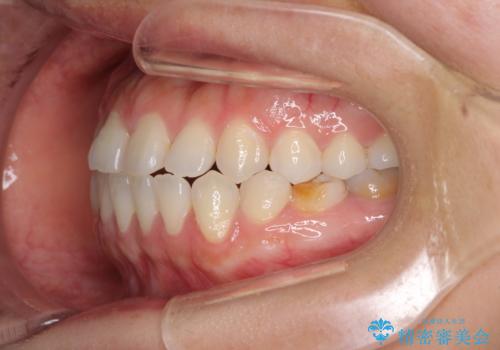

- 上下の前歯の隙間を気にして来院された患者様です。

インビザラインを用い、上下歯列のスペースを閉じていくこととしました。

治療期間中は奥歯がほとんど咬めない状態が続き、食事に大変苦労されました。

最終的には隙間もしっかりと閉じ、奥歯も咬みやすい状態でしあげることができました。